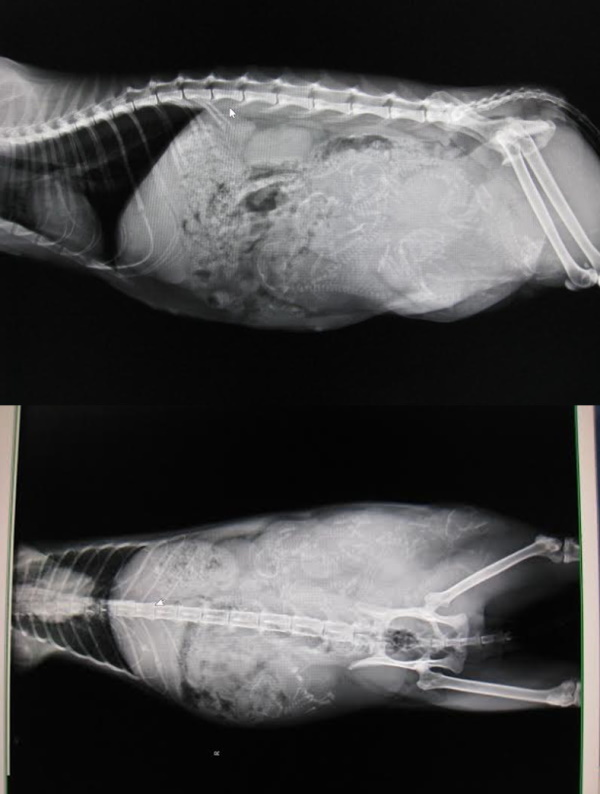

志工前去救援,發現貓咪非常親人,抱進外出籠送醫檢查,x光檢查發現腹腔赫尼亞,胎兒隨著破洞掉到後腳,當天血檢白血球過高,恐怕已經有感染的狀況,萬一引發腹膜炎,會危及母子的性命,緊急安排手術,腹中的胎兒只能盡力保全,希望母貓能平安,隔日手術縫合腹腔破洞,並將小孩取出,共有六隻,因為由腹腔掉出,有兩三隻小貓活動力較差,母貓清醒後因為腹腔壓力改變,感到非常不舒服,也有可能因為沒有生產的過程,他不願意接近小貓,一看到人就倒地討摸摸的她,拒絕小貓靠近,也不願意哺乳,醫師緊急通知由志工帶回人工餵奶,每隻小奶貓都比正常奶貓小了三之一,活動力較差懶洋洋的,志工每三十分鐘一兩滴奶水餵養,慢慢的其中三隻小貓越來越有活力,但另外三個小朋友飛走了,我們都盡力了,也謝謝志工幫忙找尋已經哺乳結束的貓媽媽,經過檢驗隔離確認身體狀況良好,擔任起三小貓的哺乳的重責大任,玳瑁媽媽雖然有點小緊張,疑惑的看著小奶貓,夜深人靜,充滿愛心的她開始認真當起奶媽的角色...